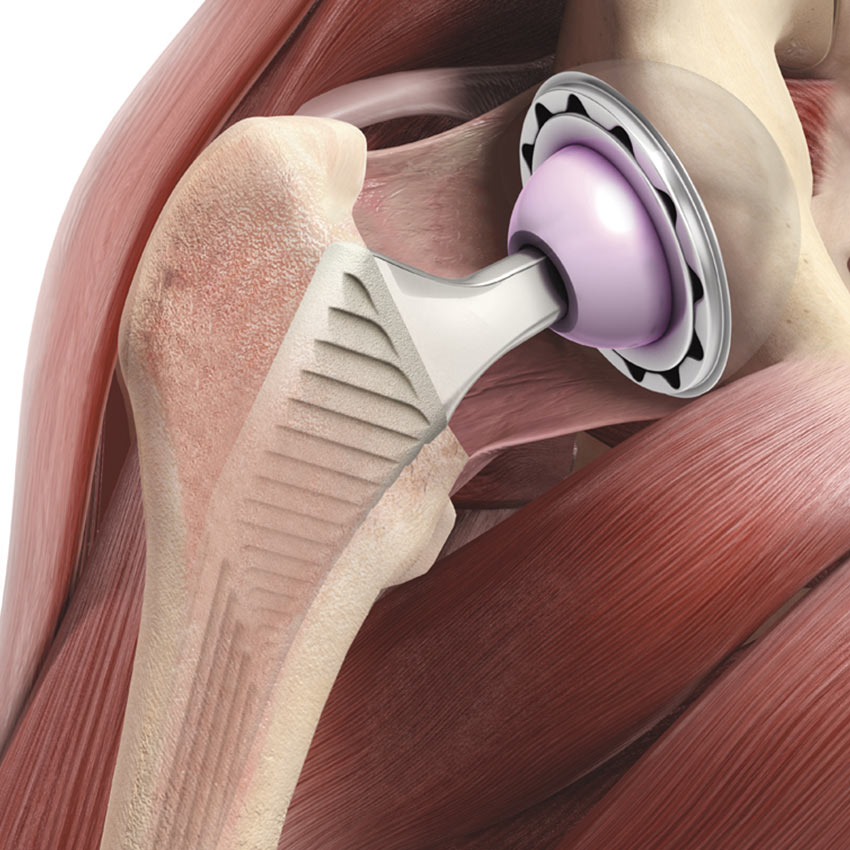

Eine Schulter-Endoprothese, auch Schulterprothese genannt, ist dem natürlichen menschlichen Schultergelenk nachempfunden. Es kann sowohl der Oberarmkopf als auch die Schulterpfanne ersetzt werden – oder beides.

Die Wahl des Implantats hängt von der Funktion der Muskulatur ab, die das Schultergelenk umgibt. Denn diese Muskeln, die sogenannte Rotatorenmanschette, führen und stabilisieren das Schultergelenk. Ist die Gelenkfläche durch Arthrose oder einen Mehrfragmentbruch zerstört, die Rotatorenmanschette jedoch intakt, brauchen wir nur die Oberfläche des Oberarmkopfes zu ersetzen. In speziellen Fällen ist die Überkleidung der Gelenkfläche der Schultergelenkspfanne (Glenoid) mit Polyethylen erforderlich.

Nach Implantation eines künstlichen Gelenkes